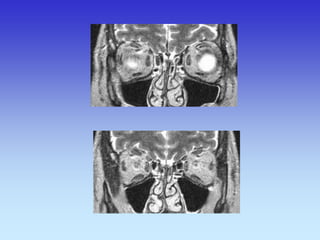

PARANAZALNI SINUSI i ORBITE

CT- SINUSA KORONARNI SLOJ (od naprijed prema straga)

1. Etmoidni sinus

2. Donja nosna školjka

3. Srednjanosna školjka

1

2

3

CT- SINUSA KORONARNI SLOJ

1.Maksilarni sinus

2.Septum nasi

3.Orbita